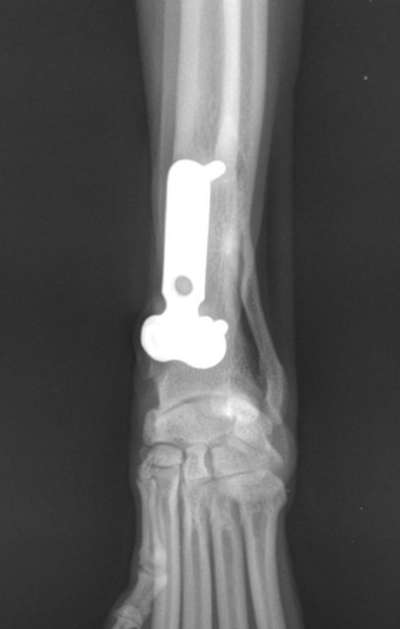

Hallo liebe Community, unserer Hündin Terika (ca. 5 Jahre) muss leider die Metallplatte aus der linken Pfote entfernt werden. Sie ist jetzt 3 Jahre bei uns und knickte jetzt vermehrt mit der Pfote beim Laufen immer weg. Die Platte muss ihr damals in Kroatien schon gesetzt worden sein. Dies hatten wir auch nur durch Zufall festgestellt. Nun meine Frage: hat jemand schon Erfahrungen mit solch einen Eingriff gemacht? auf was können wir uns so einstellen? Schonen und Kragen? Freu mich über eure Rückmeldungen.

Um die Platte zu entfernen wird Terika einer Operation unterzogen. Hierbei wird die Haut im Bereich des Implantats eröffnet und das Muskelgewebe bis zum Knochen freipräpariert. Anschließend wird das Implantat aus dem Knochen entfernt. Nach Entfernung des Implantats wird die eröffnete Haut durch eine Naht verschlossen. Je nach Möglichkeit erhält Terika einen Verband, oder die Naht wird nur durch ein Pflaser geschützt. Egal, welche Variante angewandt wird, ist es sehr wichtig, dass Terika nicht an der Wunde leckt oder knabbert. Um dies sicher zu verhindern, sollte Terika bis zum Ziehen der Fäden 12-14 Tage nach Operation zur Sicherheit Tag und Nacht einen Halskragen tragen.

Nach der Operation sind in dem Bereich, in dem die Schrauben des Implantats saßen, kleine Löcher im Knochen. Diese stellen für aber gewöhnlich kein Problem dar und der Knochen hat in der Regel eine ausreichende Stabilität. Die Löcher wachsen nach einigen Wochen zu. Dennoch ist es sinnvoll, Terika in den ersten Tagen ruhig zu halten und nur kontrolliert an der Leine zu bewegen. Die Stabilität des Knochens kann nach Entfernung der Implantate nochmal genau beurteilt werden. Dein Tierarzt/deine Tierärztin kann dir nach Entfernung eine Einschätzung geben, ob eine Ruhighaltung über einige Tage notwendig ist.